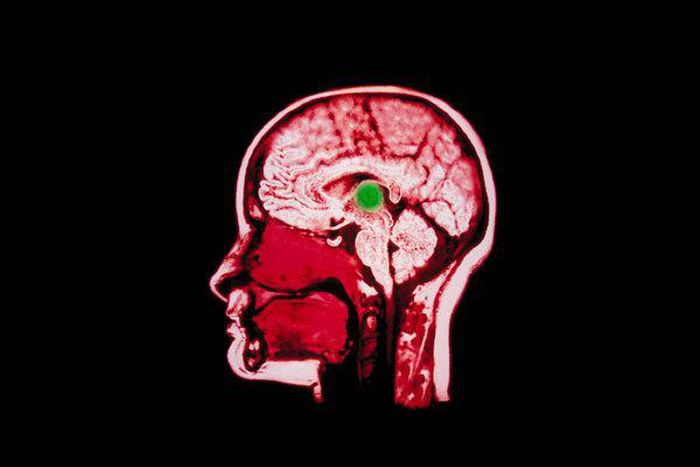

In the surgery, performed this past summer, Henderson threaded two electrodes into the thalamus, a switching center deep in the brain. Precision was critical. Before the surgery, the team did extensive work to identify specific regions in the brain that support activation of the frontal cortex, which is involved in thinking and planning, and the basal ganglia, which supports learning and memory.

“Operating on the thalamus is pretty routine,” Henderson said in an email. “This is a different target, though, and difficult to hit because of its size and shape. So a bit of extra precision is called for.”

The electrodes were connected to a pacemaker device, implanted in the woman’s chest wall, that produced active current for 12 hours a day, from morning to evening.